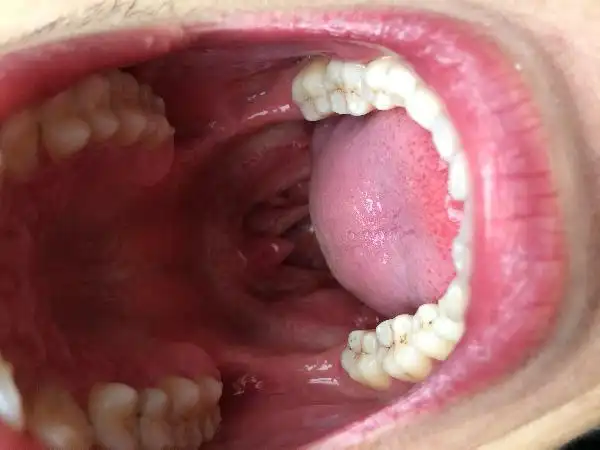

求问舌头这样子是hpv吗

请问这是口腔尖锐湿疣

hpv)感染引起的皮肤和黏膜病变,常见于生殖器周围,但它也可以在口腔

口腔也会感染hpv病毒口啪需谨慎

舌头尖锐湿疣症状 - 知乎